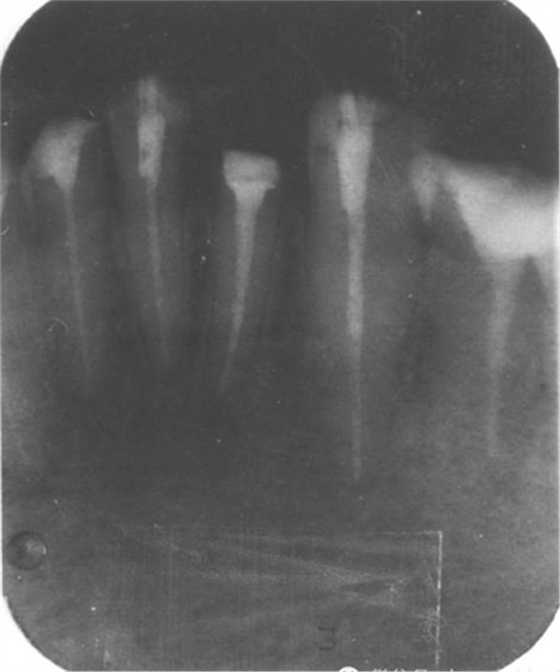

4.用匹配的鉆石擴大至最初的直徑,用X光檢查。

5.重新安裝新的樁核等材料。通過X光片檢查以上步驟。

手術(shù)后